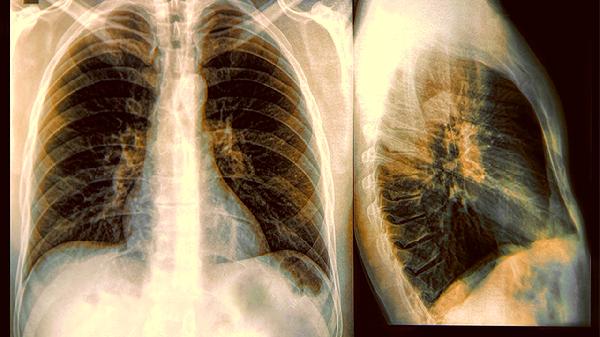

2.外形特征会说话

边缘光滑像鹅卵石的通常很安全,毛玻璃样结节需要更多观察时间。最该关注的是那些带毛刺的分叶状结节,就像仙人掌一样张牙舞爪的形态风险较高。

3.位置透露小秘密

上肺叶的结节比中下肺叶更值得关注,这个区域是肺癌好发地。但要是双肺多发散在的小结节,反而可能是陈旧性.病变的表现。